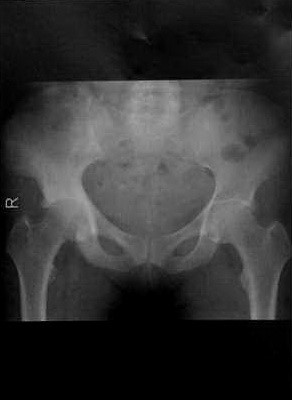

Женщина 67 лет с болезнью Педжета , поражающей правую половину таза. Рентгенологическое изображение таза. Склеротическая стадия заболевания с преобладанием склероза в правой половине таза. Поражение обычно не пересекает крестцово-подвздошного соединения. Артропатия Педжета правого тазобедренного сустава.